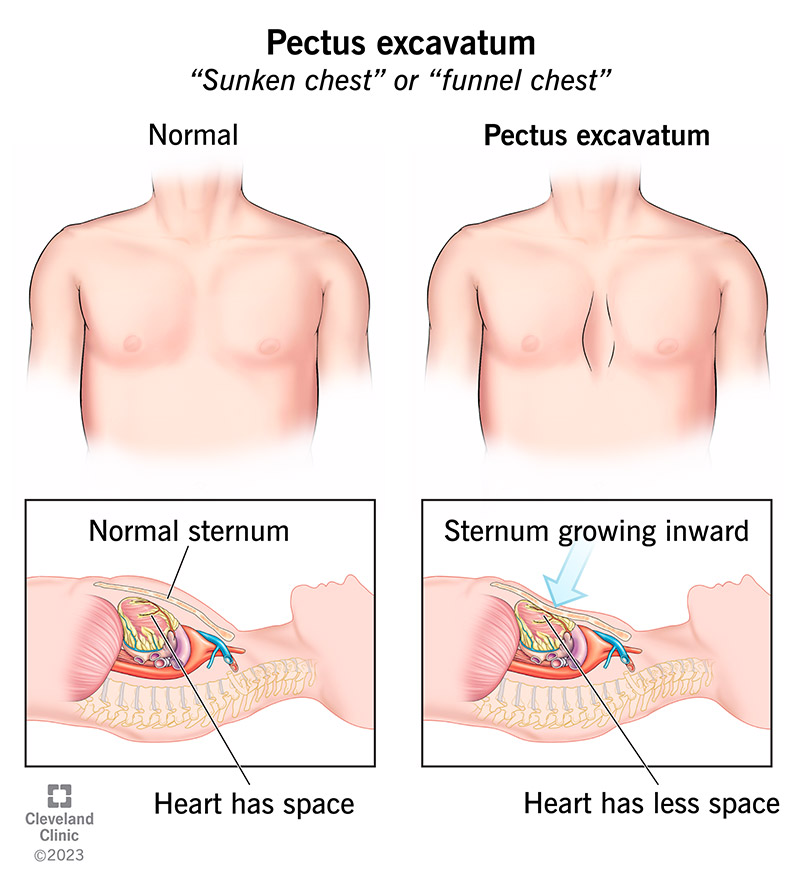

Funnel chest (ફનેલ ચેસ્ટ):

- ફનેલ ચેસ્ટને ‘પેક્ટસ એક્સકેવેટમ ‘(Pectus excavatum) ‘સંકન ચેસ્ટ’ અને ‘કોબ્લર્સ ચેસ્ટ’ તરીકે પણ ઓળખવામાં આવે છે.

જેમાં પેક્ટસનો અર્થ ચેસ્ટ, અને એક્સકેવેટમનો અર્થ ખાડો થાય છે. - પેક્ટસ એક્સકેવેટમ એ એબનોર્મલ કન્જાયનેટલ કન્ડિશન છે. જેમાં સ્ટરનમ એ અંદરની બાજુ ખેંચાયેલ હોય છે એટલે કે સ્ટરનમ ડીપ્રેશેડ થયેલ જોવા મળે છે અને અંદરની બાજુ ગ્રો થાય છે.

- ફનેલ ચેસ્ટમાં એન્ટેરિયર પોસ્ટેરીયર ડાયામીટરમાં ઘટાડો જોવા મળે છે.